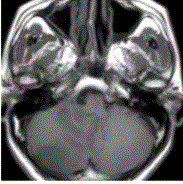

问题 患者女,75岁,突发偏瘫、头痛、头晕10h。既往有高血脂、糖尿病史。MRI表现如下图。 初步诊断为

选项 A.脑星形细胞瘤 B.脑急性血肿 C.蛛网膜下隙出血 D.脑急性梗死 E.急性化脓性脑炎

答案 D